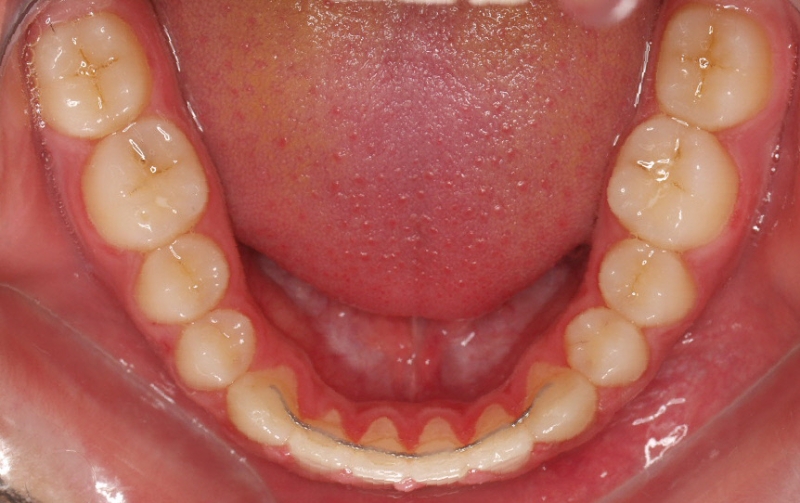

Chica de 17 años tratada en 1 año con stripping en los dientes inferiores

El stripping consiste en la reducción interproximal del esmalte entre los dientes posteriores y anteriores, así obtenemos espacio para alinear los dientes apiñados.